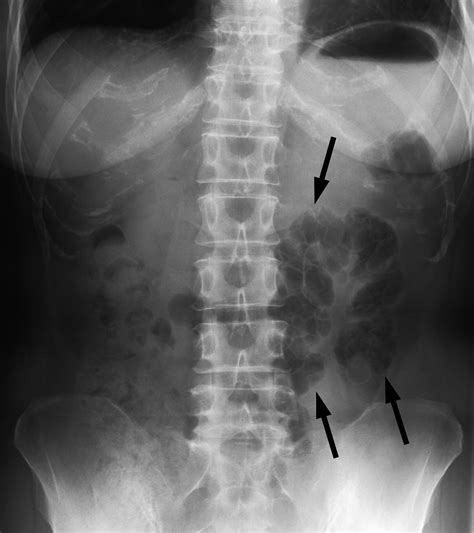

Abdominal X-ray Can show radiolucent areas along the bowel wall, but lacks sensitivity.

When reviewing imaging, radiologists look for the specific appearance of "bubbly" gas collections along the serosal or submucosal surfaces. Differentiating these cysts from free air (pneumoperitoneum) is the most critical step for the radiologist to ensure the patient is not facing a surgical emergency.